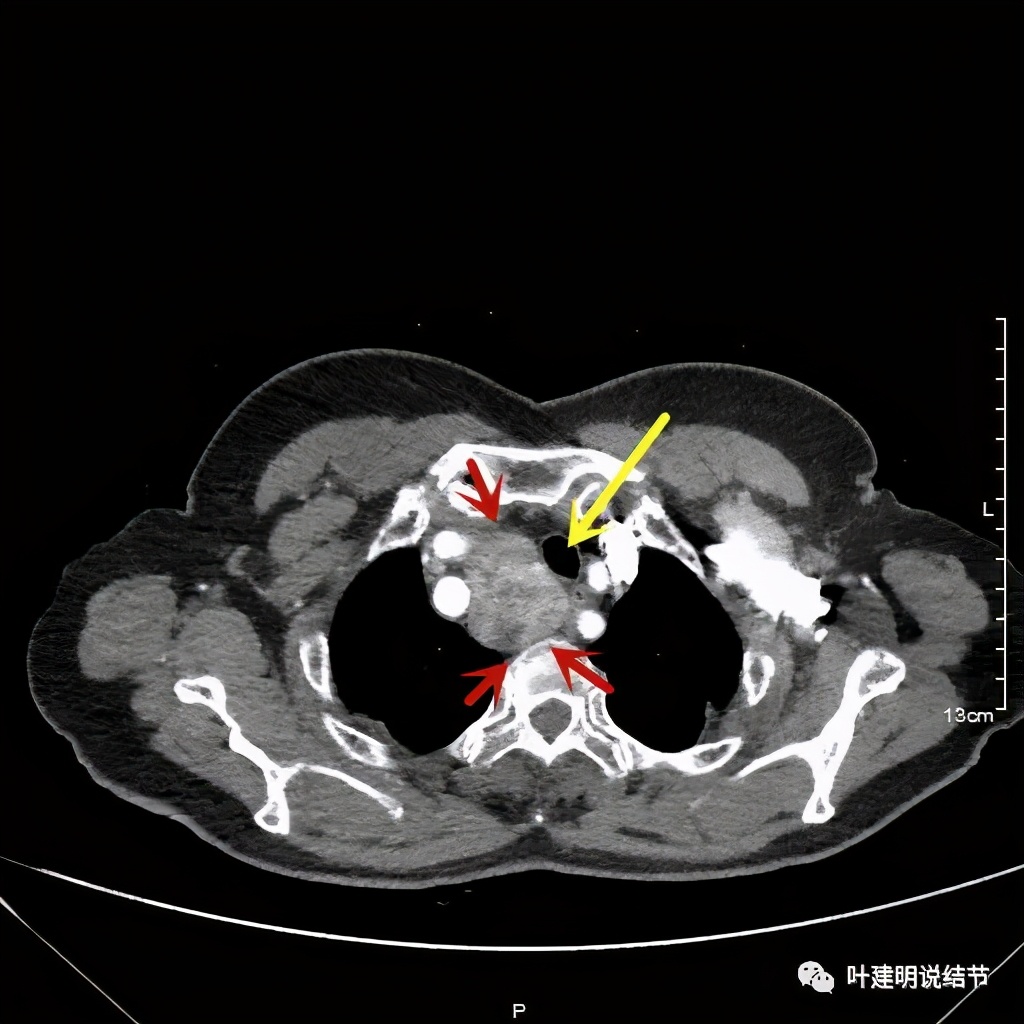

上图红色示肿瘤,黄色示气管,而且肿瘤密度不均杂乱

红色示肿瘤

上图红色示肿瘤,粉色示肿瘤与气管关系密切,而且肿瘤密度不均杂乱